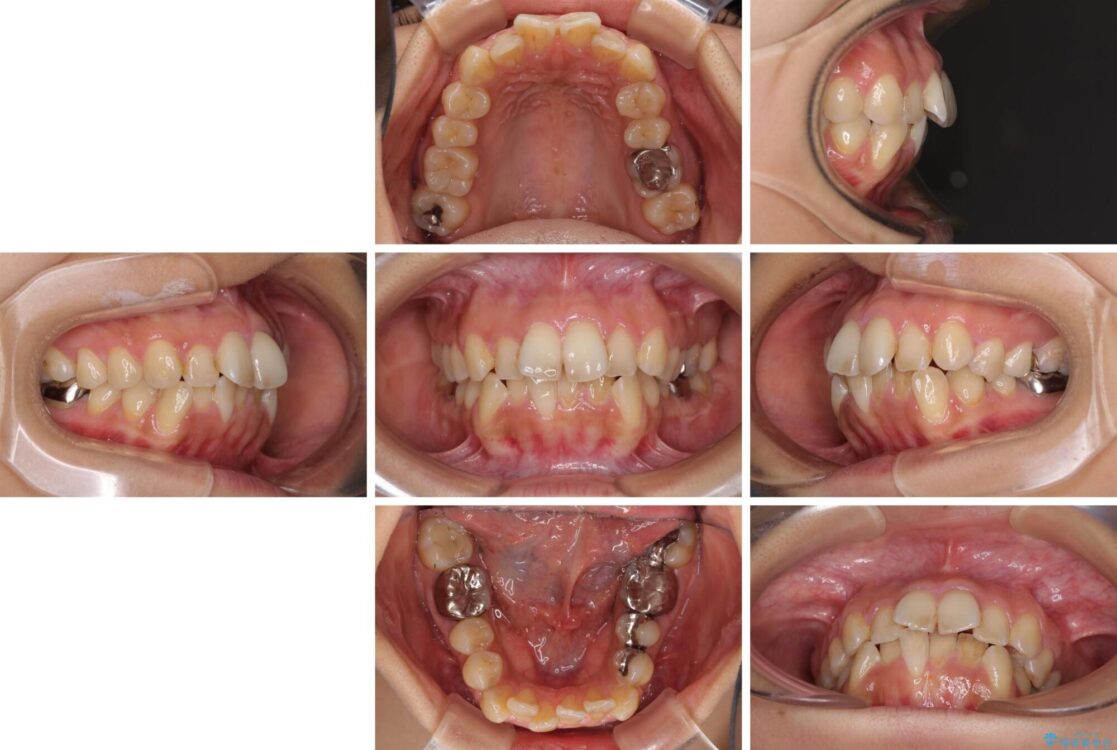

治療後

• デコボコと口元の突出感 ハーフリンガルでの抜歯矯正 治療後画像